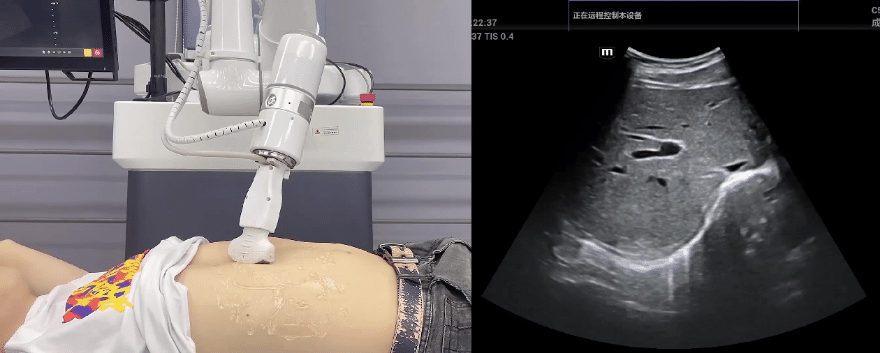

艾利特協(xié)作機(jī)器人搭載庫(kù)柏特自主研發(fā)的機(jī)器人遙操作、多模態(tài)數(shù)據(jù)采集與處理、機(jī)器人模仿學(xué)習(xí)、機(jī)器人力位控制等技術(shù)升級(jí)變革傳統(tǒng)超聲,可實(shí)現(xiàn)遠(yuǎn)程+自主超聲掃查與診斷,從傳統(tǒng)遠(yuǎn)程超聲僅能對(duì)話會(huì)診變革升級(jí)為能對(duì)話、能操作,使得基層患者可就近享受異地三甲專家掃診服務(wù)。實(shí)現(xiàn)專家端與患者端遠(yuǎn)程連接,并支持專家端與多路患者端自由切換控制。

EC66協(xié)作機(jī)器人末端可搭載主流品牌高品質(zhì)超聲儀,讓操作指令和影像低延遲、高精準(zhǔn)、高保真?zhèn)鬏敚_保檢查可靠、醫(yī)患放心;智能力控等三重防護(hù)系統(tǒng),確保患者舒適、安全。

艾利特協(xié)作機(jī)器人與超聲深度打通,最大程度保留醫(yī)生左右手同時(shí)操作傳統(tǒng)超聲的習(xí)慣,并改善其舒適性,超聲檢查實(shí)際應(yīng)用場(chǎng)景展示如下:

肝臟、膽囊、胰腺掃查